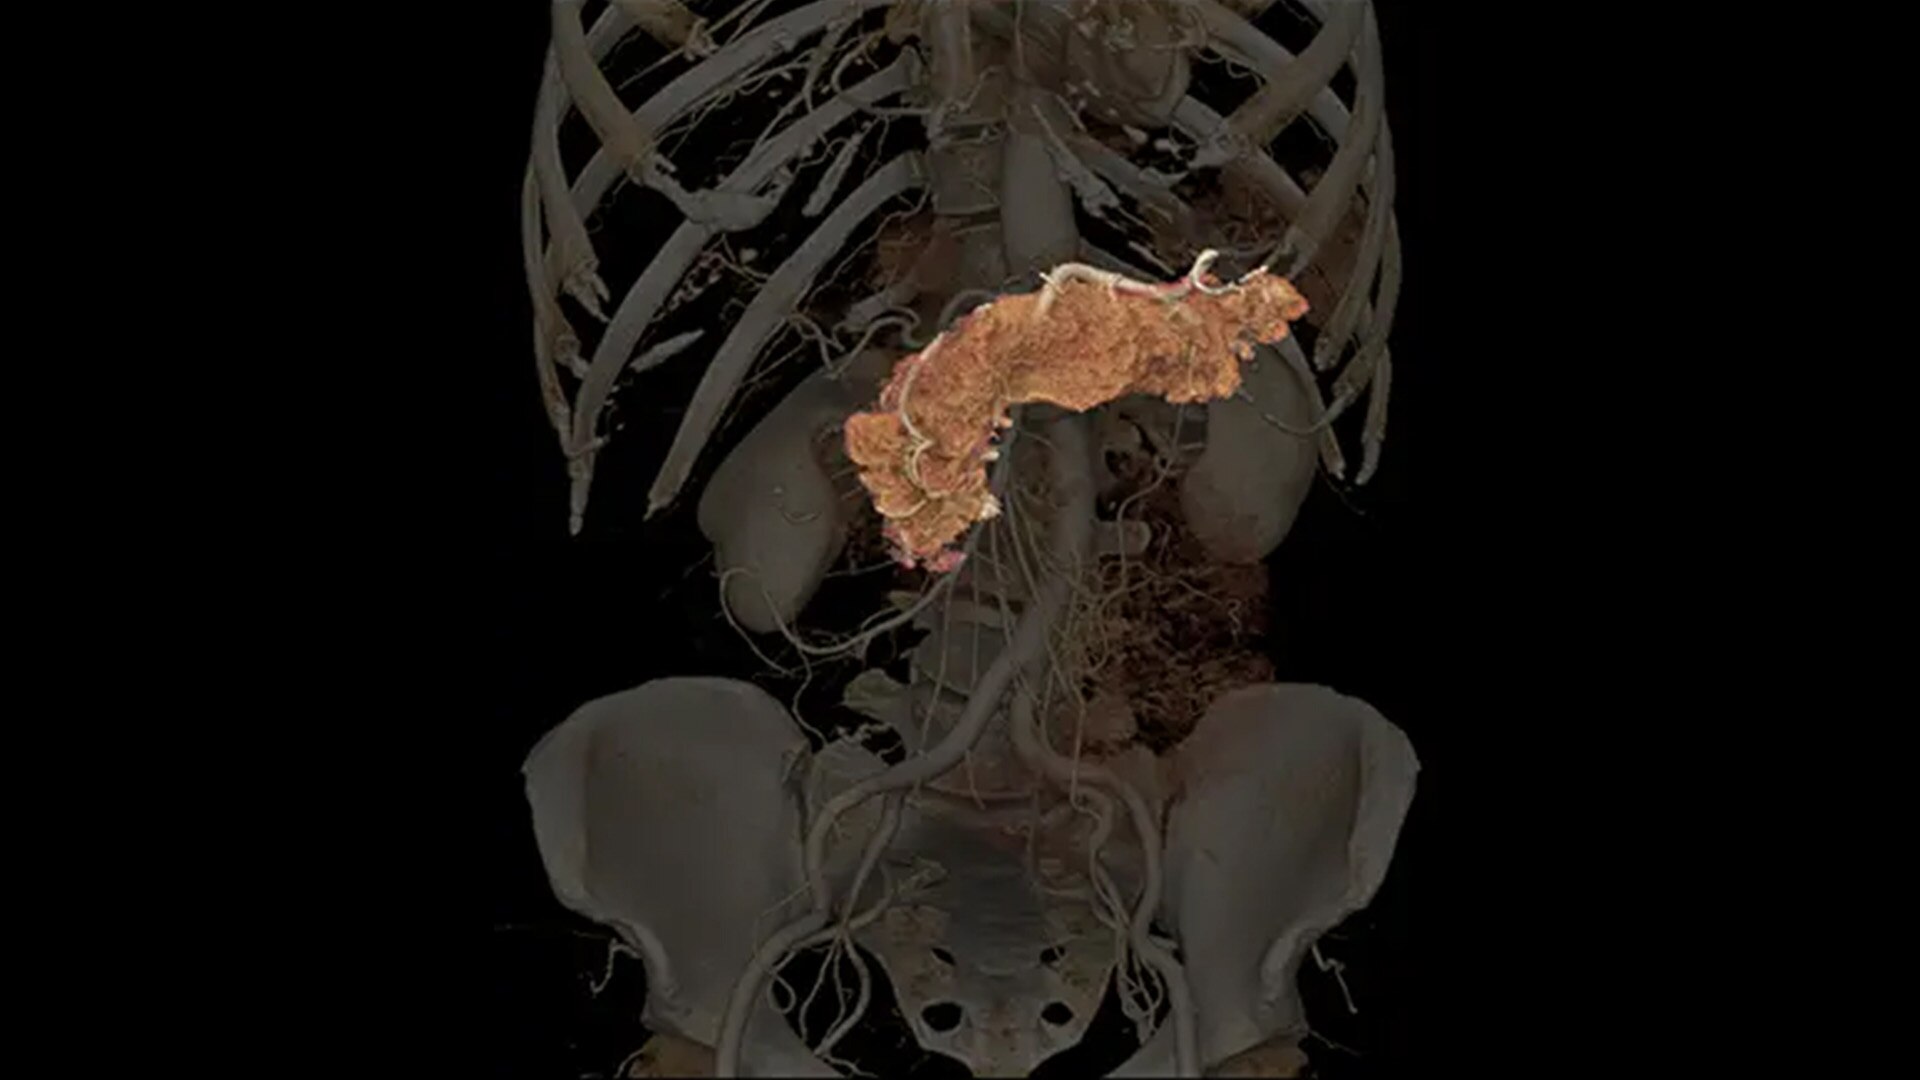

for the realization of the full potential of photon-counting CT in oncology, cardiology, neurology and more.

Photonova Spectra delivers ultra-high-definition imaging with wide coverage, enabling fast acquisition and precise visualization of anatomical structures. Engineered with on-demand spectral imaging available for every scan, it helps to support clinicians in detecting, characterizing, and monitoring disease with confidence and ease.

Photonova Spectra is also designed to enhance material separation for tissue characterization and disease quantification, bringing potentially greater diagnostic confidence in every acquisition across care areas.